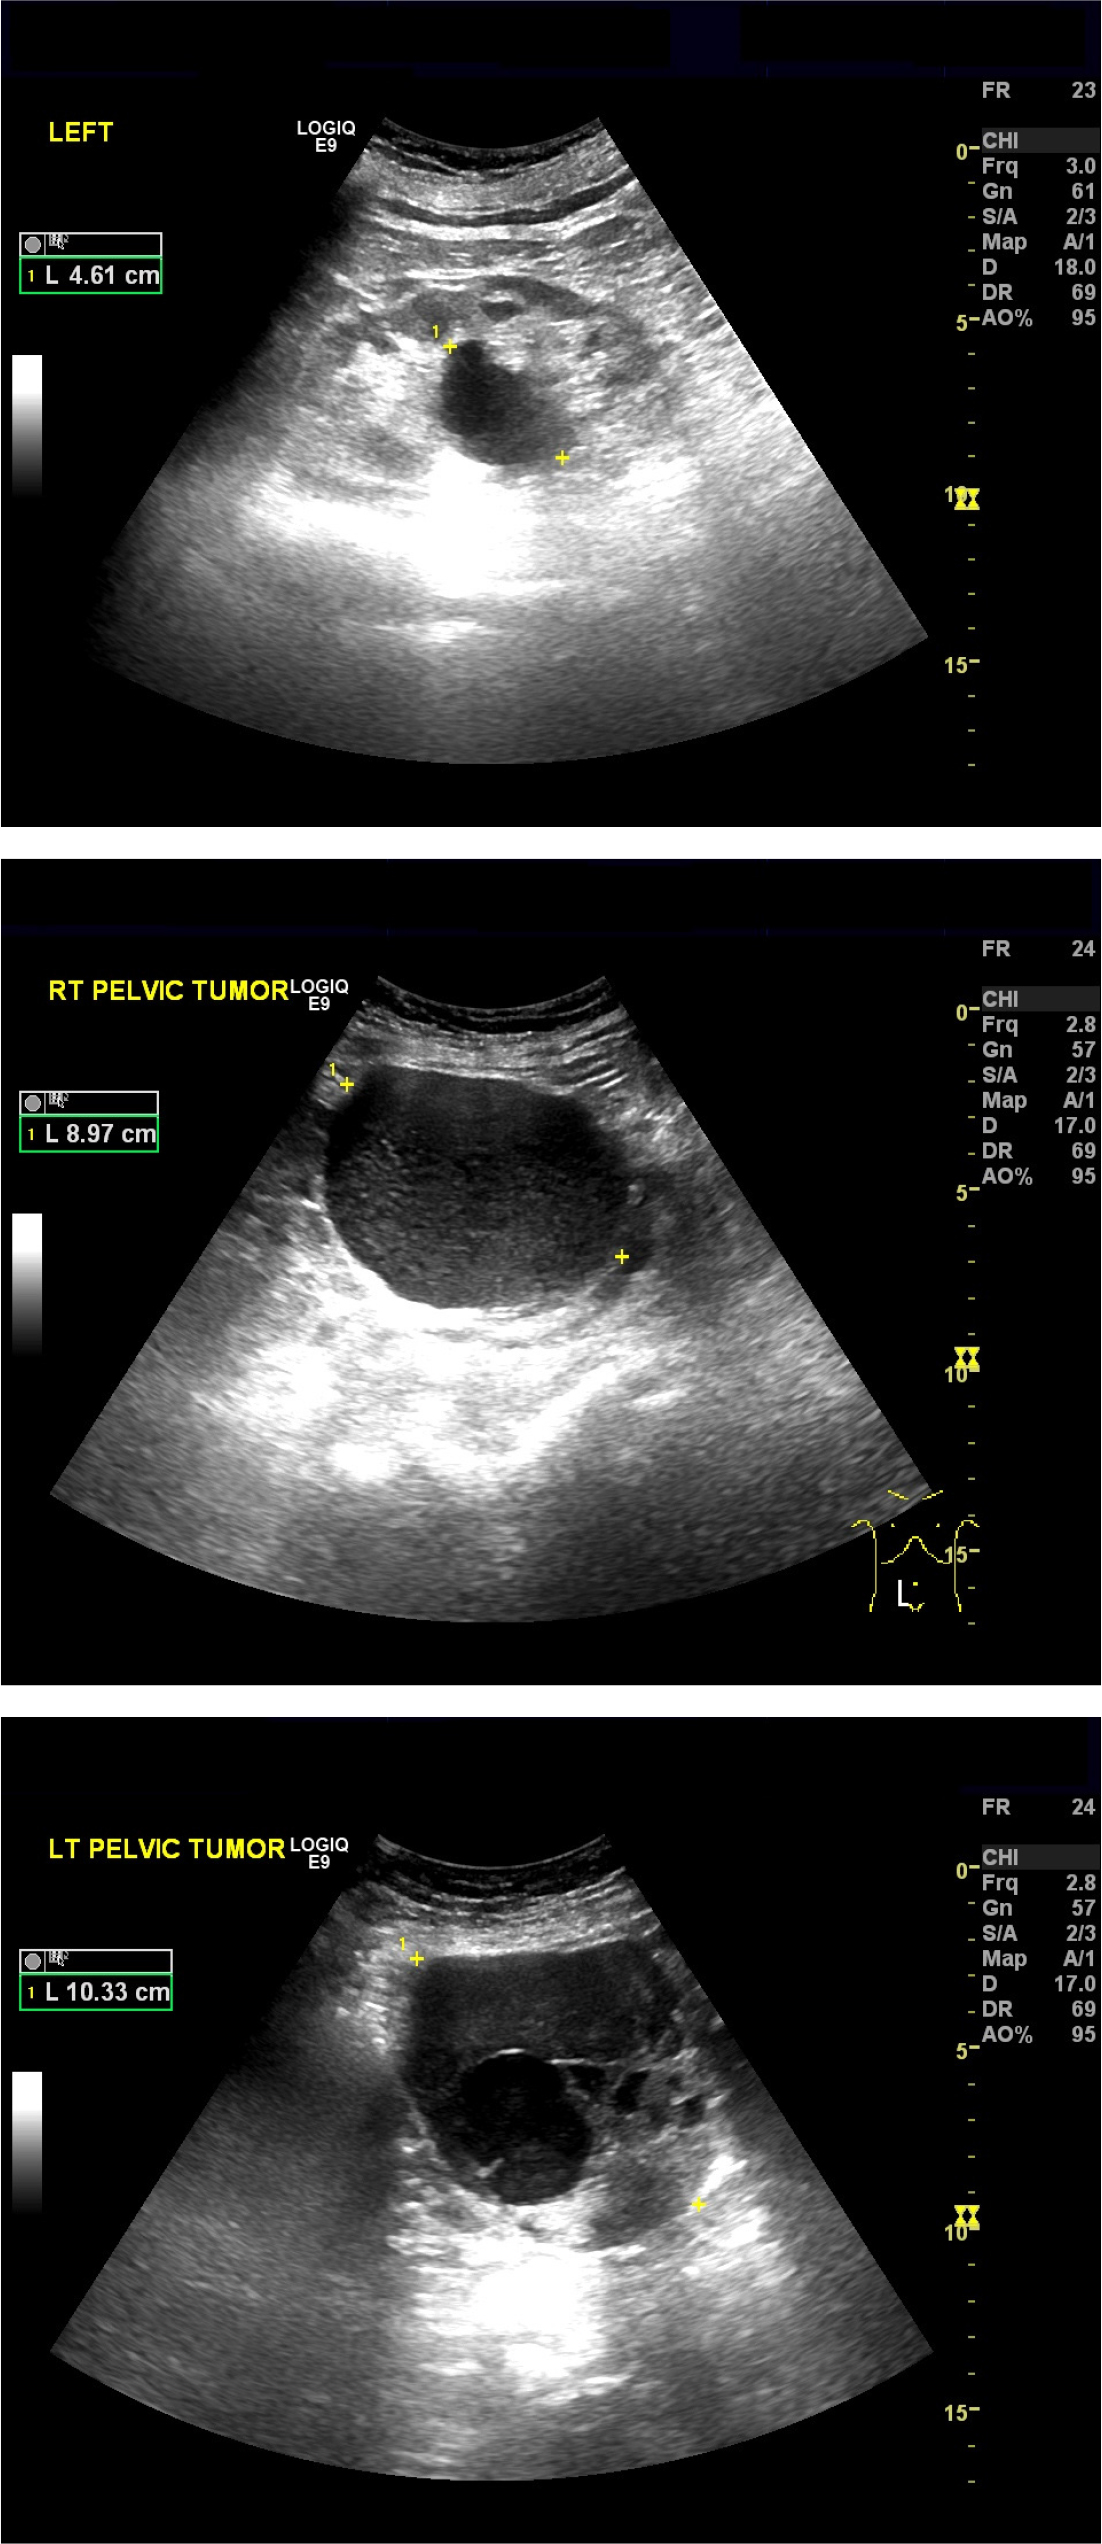

86세의 여성이 배뇨 곤란이 갑자기 심해져서 내원하였다. 환자는 20년 전 요실금 수술을 받은 병력이 있다. 3년 전부터 본원에서 야간뇨와 급박뇨를 치료받던 중 외래 추적 소실 후 3개월 만에 갑자기 발생한 배뇨 곤란 증세로 내원하였다. 신체 검사에서 하복부팽만 및 전신부종소견이 있었다. 초음파검사에서 왼쪽 난소 heterogenous density solid and cystic tumor, 오른쪽 난소에 large cystic tumor 소견이 관찰되었다. 골반 CT를 시행하였고 both ovaries malignancy Krukenberg tumors, 10 cm in each sides secondary stomach tumor 소견이 관찰되었다. 환자는 대학병원으로 전원되었으나 3개월후 사망하였다.